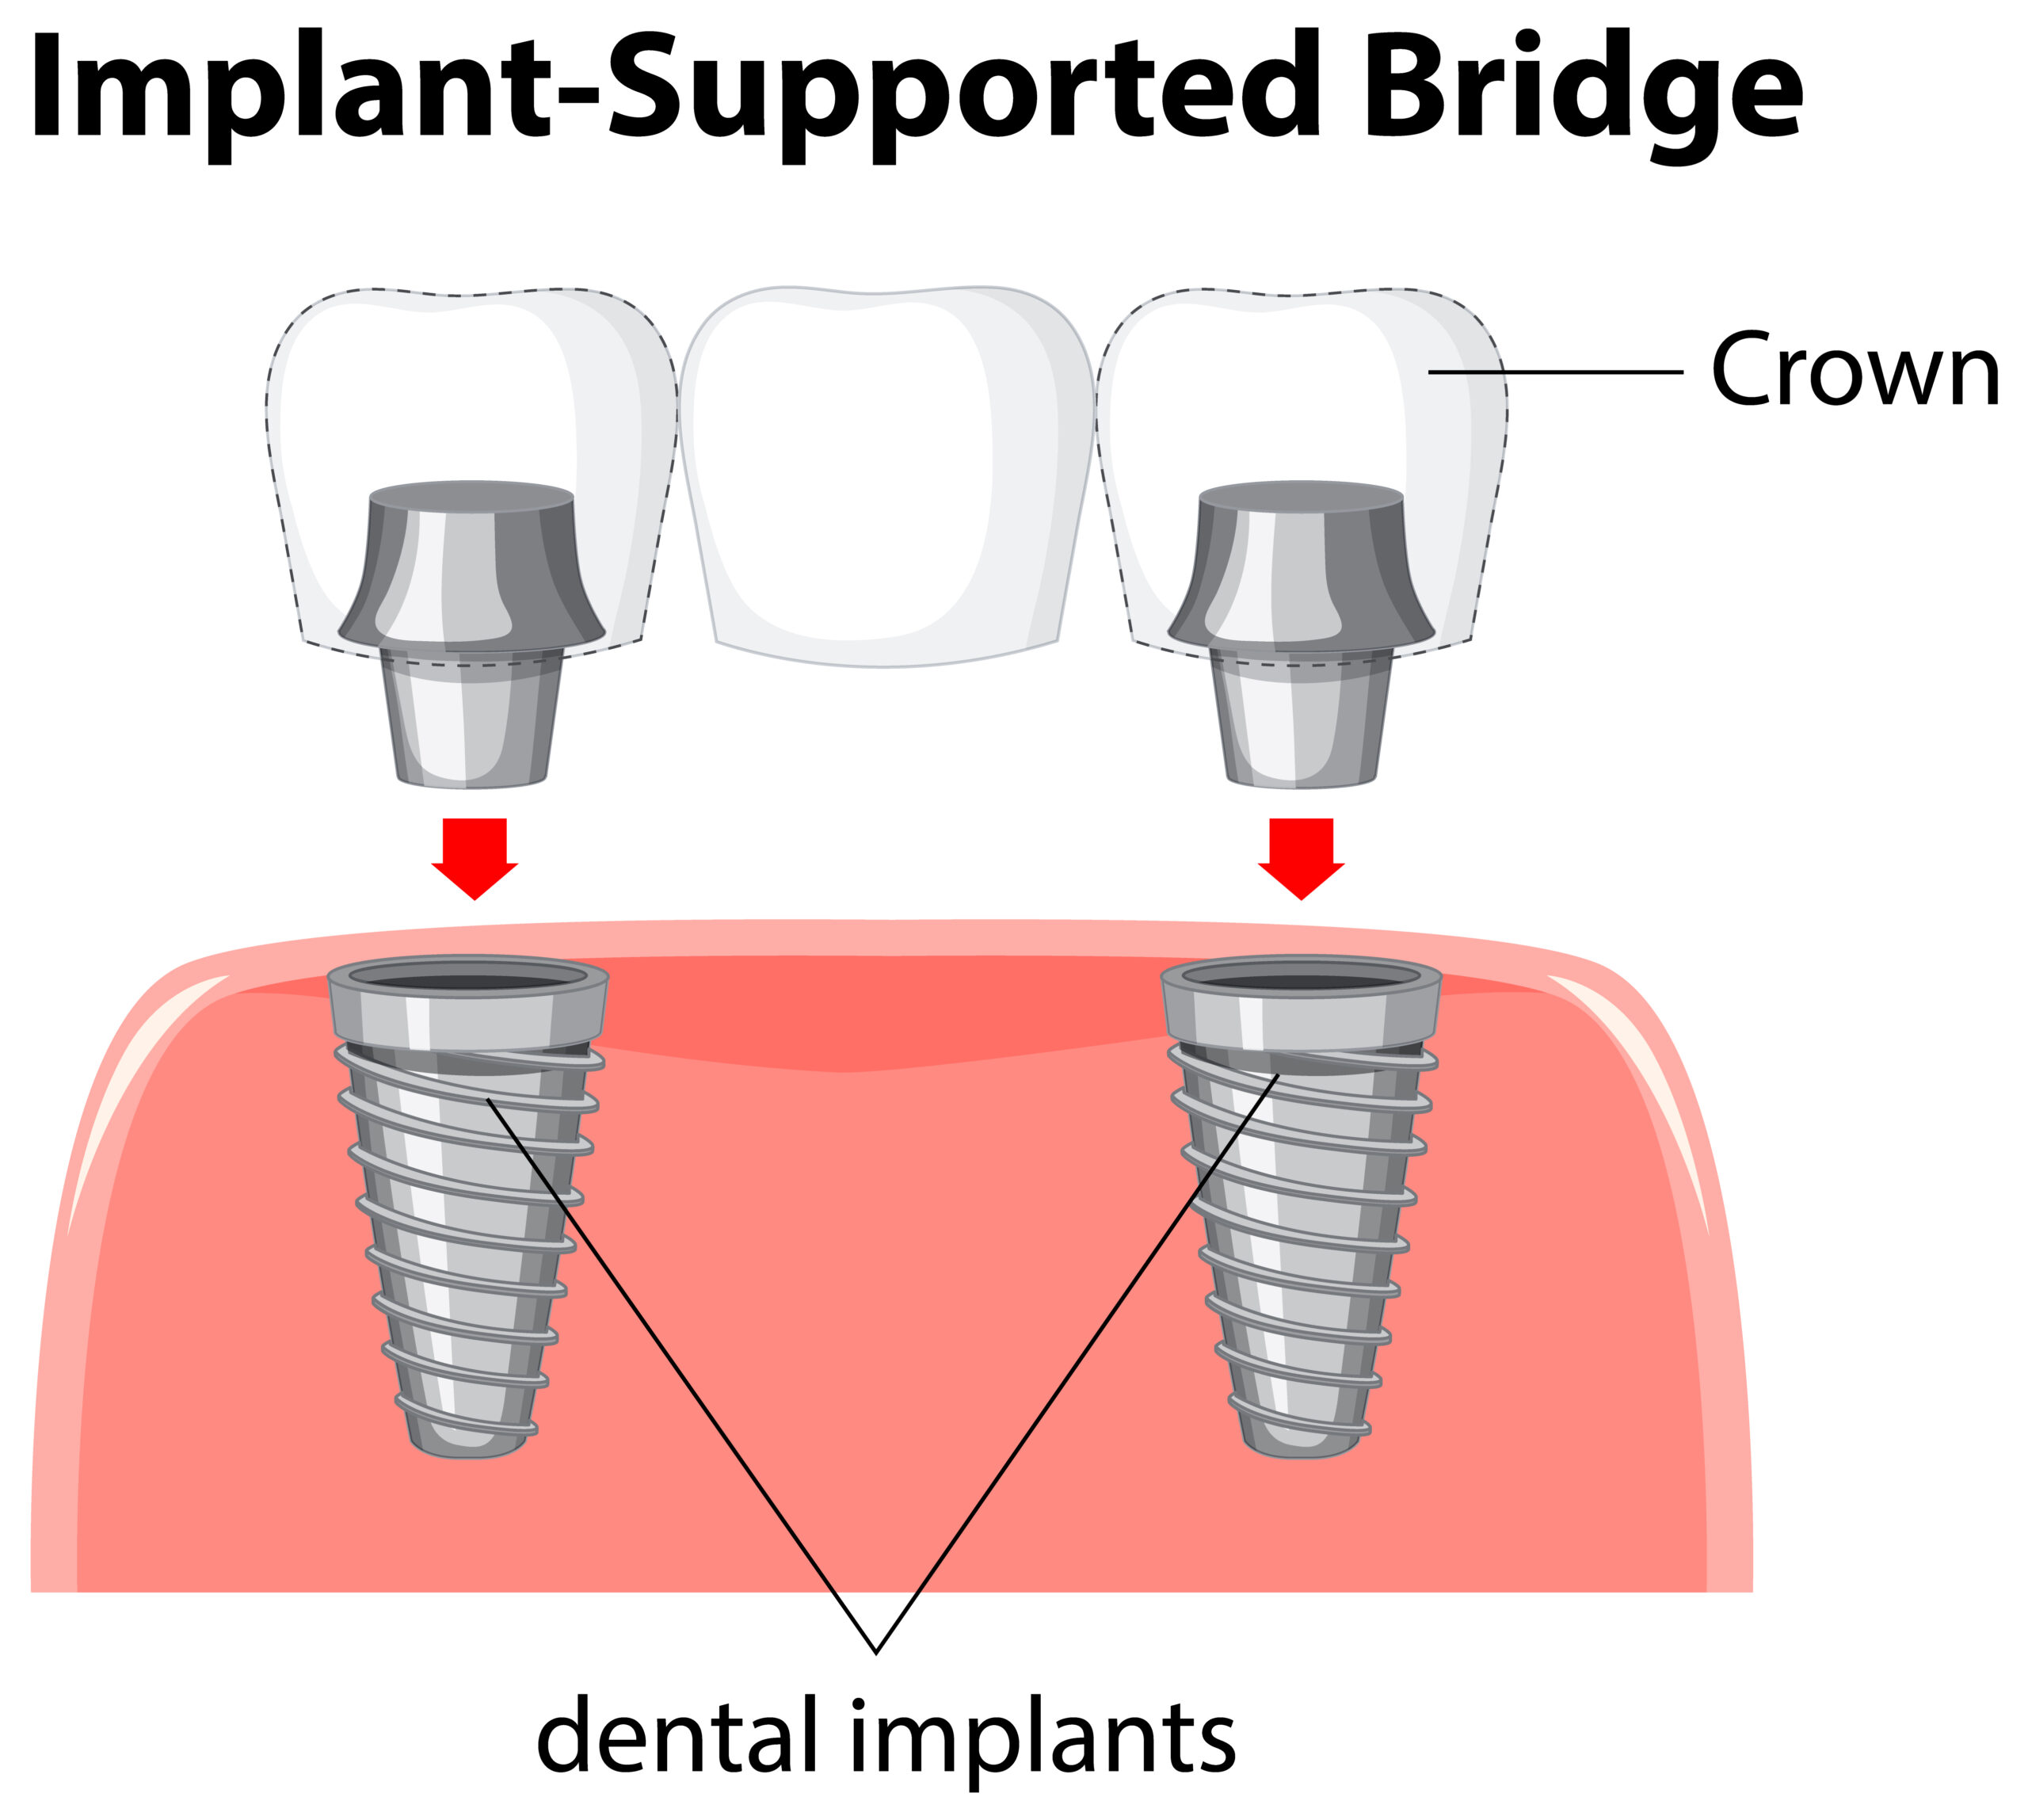

What Is an Implant-Supported Bridge? An implant-supported bridge is a dental device used to replace several missing teeth. Unlike regular bridges, this option uses dental